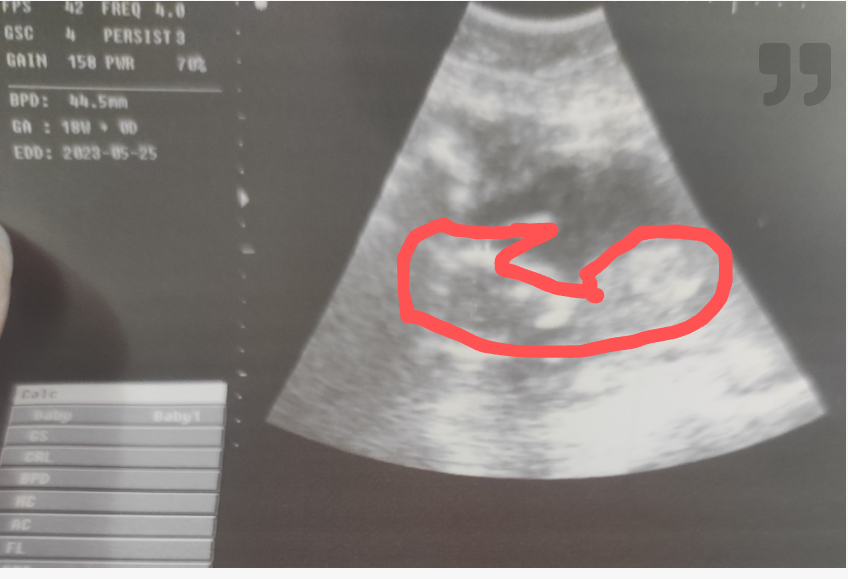

Да пия желязо но ,защо на снимката не се вижда телцето ,а само едното краче и едната ръчичка както е очертано ?

По това време на бременността така изглежда бебето, това му е телцето с ръчички и крачета, единствено мога да кажа, че видеозона е стар. На Фм в 12гс ходихте ли?

На снимката е очертано цялото тяло. Фм се прави в определи седмици, за да не я изпуснеш са ти казали така. А на предната ходила ли си? Според мен се паникьосваш излишно щом и тест за бременност правиш в 5 месец…. Карай доктора ти да ти обяснява повече, за да не ходиш на прегледи и след това да се чудиш дали има бебе на снимката. Сърце не ти ли пускат да чуеш ?